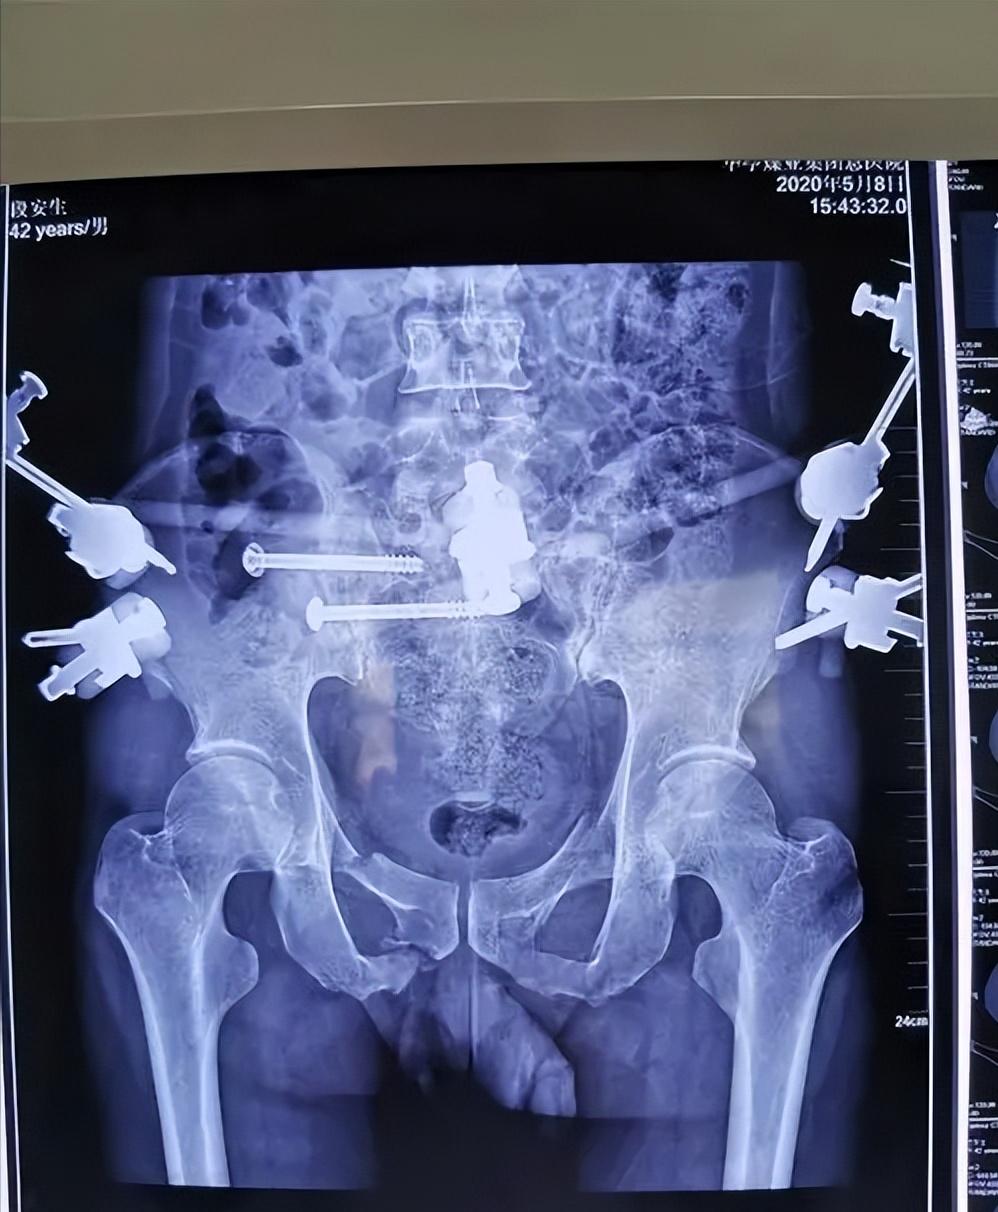

而骨盆后环在整个骨盆环中的重要性占到了60%,随着骨盆后环被损伤,骨盆稳定性也将被破坏, 而目前运用在骨盆后环的内固定主要是骶髂关节前方双钢板、后方张力带钢板、骶髂关节单枚拉力螺钉以及骶髂关节2枚拉力螺钉固定。

骶髂关节螺钉固定

IS固定具有固定效果可靠以及可进行微创操作等优点, 1989年时Matta等人第一次报道在骨盆后环损伤患者中使用骶髂螺钉固定,并且,到如今,此方法仍然是目前临床治疗骨盆后环损伤最常用的方法之一。

IS固定技术可减少患者创伤,同时手术时间大大缩短,术后感染风险也大幅减少。 但是,在IS操作过程中需要反复透视定位钉道位置,骶髂拉力螺钉的长度以及直径选择不当的话就有可能对重要神经造成损伤,出现不可挽救的并发症。

但由于和其他内固定方式相比,此内固定方式更能体现出微创理念,并且感染风险小,操作简单,固定牢固,故仍然常被使用。

在固定时,是否需要2枚螺钉固定还存争议。在骨盆前环稳定固定后,后环是否使用2枚螺钉固定并无差别。通过生物力学分析证明,前环不稳时,2枚螺钉的固定效果优于1枚螺钉。

从生物力学稳定方面来看, 两枚骶骼螺钉的固定效果要优于单枚拉力螺钉固定,因为单枚拉力螺钉无法做到对抗旋转移位或者对抗旋转移位的能力小。